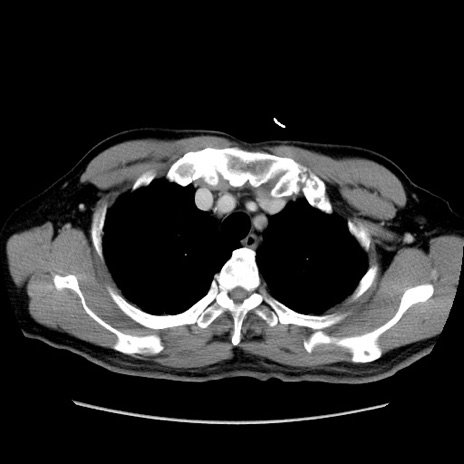

症例34(横断像)

【症例】60歳代 男性

【主訴】右鼠径部膨隆

【現病歴】1年程前より右鼠径部膨隆あり。自己にて還納可能だったため放置していた。3時間前より右鼠径部の脱出を認め、還納困難となり受診。

【既往歴】高血圧

【身体所見】右鼠径部に小児頭大の膨隆あり。弾性硬であり、用手還納は困難。左鼠径部にも膨隆を認める。脱出はなし。

【データ】WBC 15500、CRP 測定なし